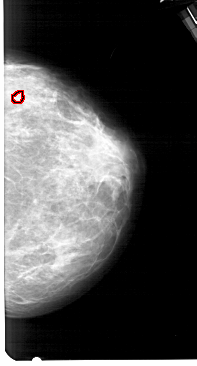

A_1546_1.RIGHT_MLO

RIGHT_MLO LINES 5491 PIXELS_PER_LINE 2941 BITS_PER_PIXEL 12 RESOLUTION 43.5 OVERLAY

FILE: A_1546_1.RIGHT_MLO.OVERLAY

TOTAL_ABNORMALITIES 1

ABNORMALITY 1

LESION_TYPE CALCIFICATION TYPE PLEOMORPHIC DISTRIBUTION CLUSTERED

ASSESSMENT 4

SUBTLETY 1

PATHOLOGY BENIGN

TOTAL_OUTLINES 1

BOUNDARY